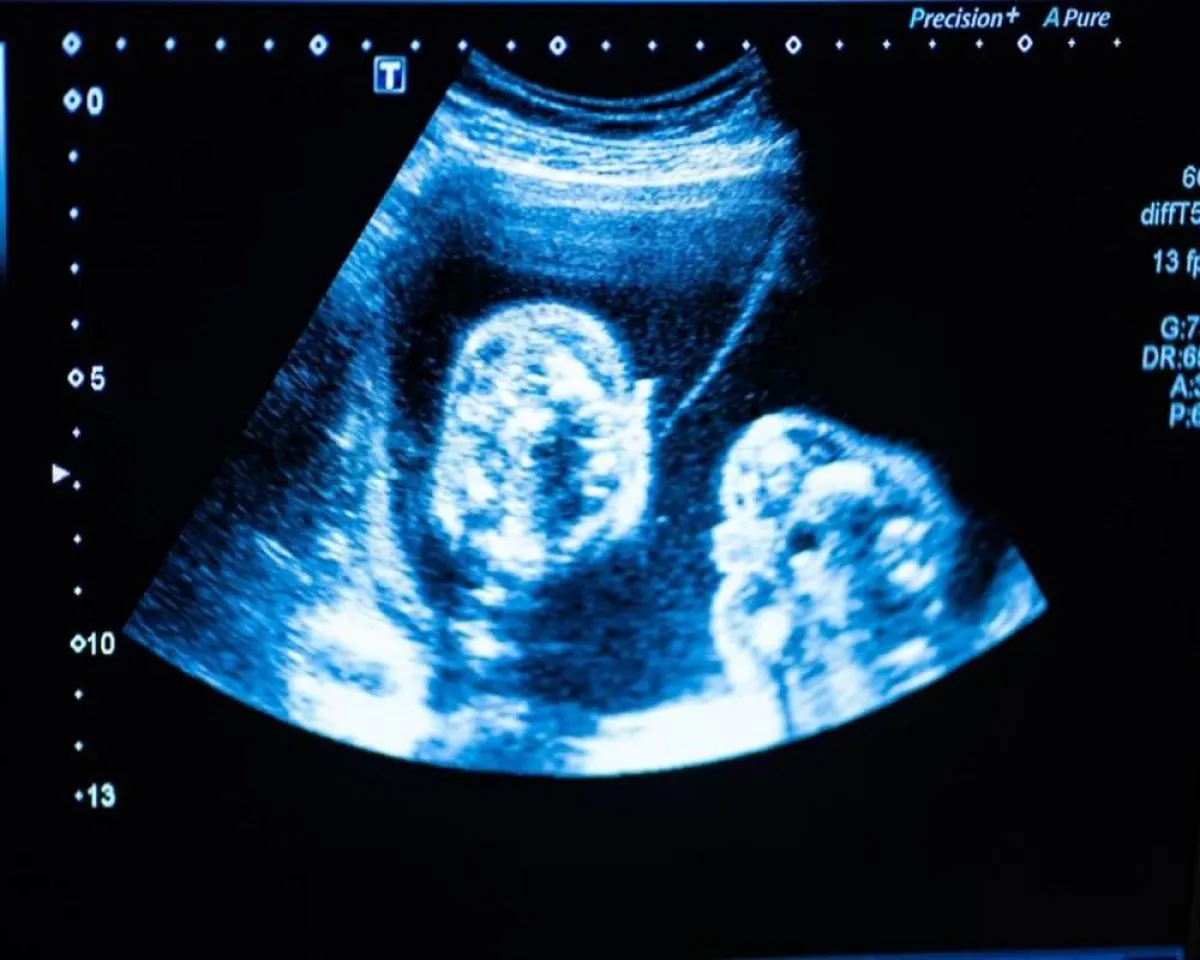

قد لا تدرك الكثير من النساء أنهن تعرضن لإجهاض مبكر إذا حدث ذلك بعد فترة وجيزة من غياب الدورة الشهرية. غالباً ما يشخص الأطباء الحمل الكيميائي عندما يكون لديك اختبار حمل إيجابي ويبدأ الحيض بعد ذلك. ويمكن أيضاً تشخيصه إذا كان هناك اختبار حمل إيجابي ولكن لا يمكن رؤية الجنين في الموجات فوق الصوتية.